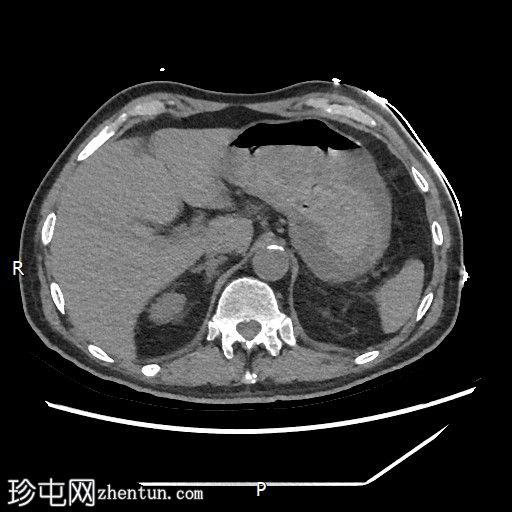

CT

轴位

平扫